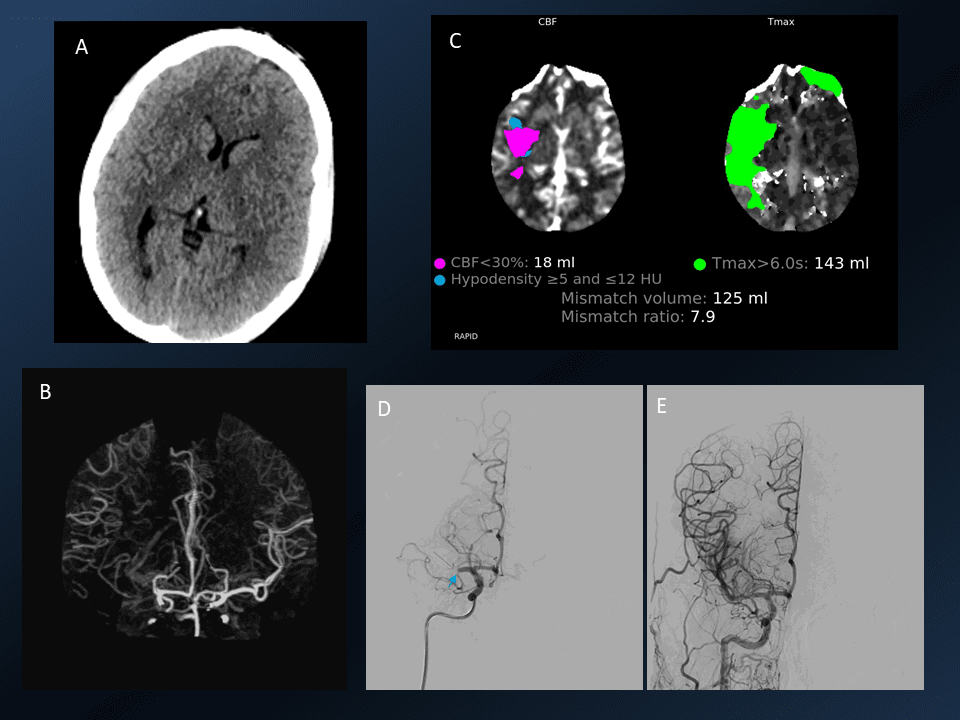

3. Mechanical Thrombectomy with aspiration only technique

Mechanical Thrombectomy with aspiration only technique CT, CT perfusion and angiogram images

Young patient with left sided dense hemiplegia while working out in gym. Time of onset 3 hrs. Plain CT demonstrates early changes of acute stroke in the right MCA territory (A). CTA confirms right M1 occlusion (B). Perfusion imaging (C) shows mismatch ratio of 7.9 with good volume of salvageable brain (green shade). DSA re-demonstrated the right M1 occlusion which was successfully removed using only suction, ADAPT resulting in TICI 3 outcome (E).